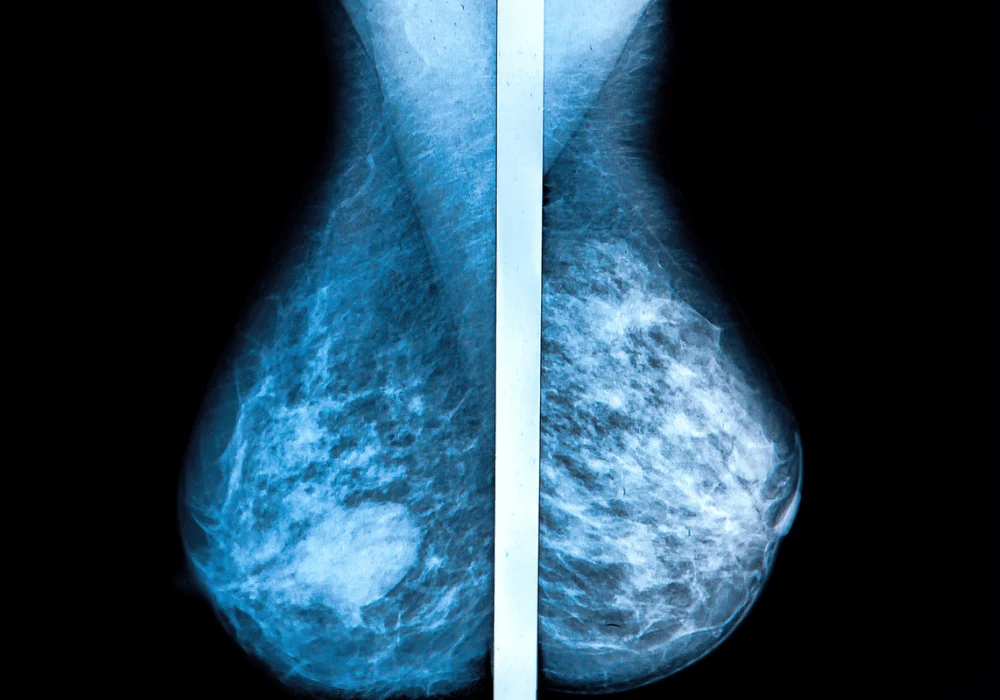

Digital breast tomosynthesis (DBT) has demonstrated improved breast cancer detection rates compared to traditional digital mammography (DM). However, cancers can still go undetected during screening, raising concerns about the accuracy and interpretation of results. The Malmö Breast Tomosynthesis Screening Trial (MBTST) investigated the effectiveness of one-view DBT versus two-view DM and explored the reasons behind non-detected cancers. This study aimed to identify the characteristics of missed cases, analyse radiographic patterns and understand the factors influencing non-detection, contributing to ongoing research into optimising breast cancer screening methods.

Radiographic analysis revealed distinct patterns in non-detected cancers. False negatives often exhibited benign-appearing densities, spiculated features and indistinct densities, making them harder to identify during initial screenings. Notably, cancers with calcifications and architectural distortions were also frequently misinterpreted. The study emphasised that standard screening views might not always provide sufficient visual clarity, leading to misinterpretations or oversight.

Imaging interpretation errors also played a significant role in non-detection. Many cancers classified as minimal signs or non-visible had subtle features that were either overlooked or misclassified as non-suspicious. The reliance on a single DBT view further limited the detection of certain tumour presentations, suggesting the need for enhanced imaging protocols or multiple views for improved accuracy.